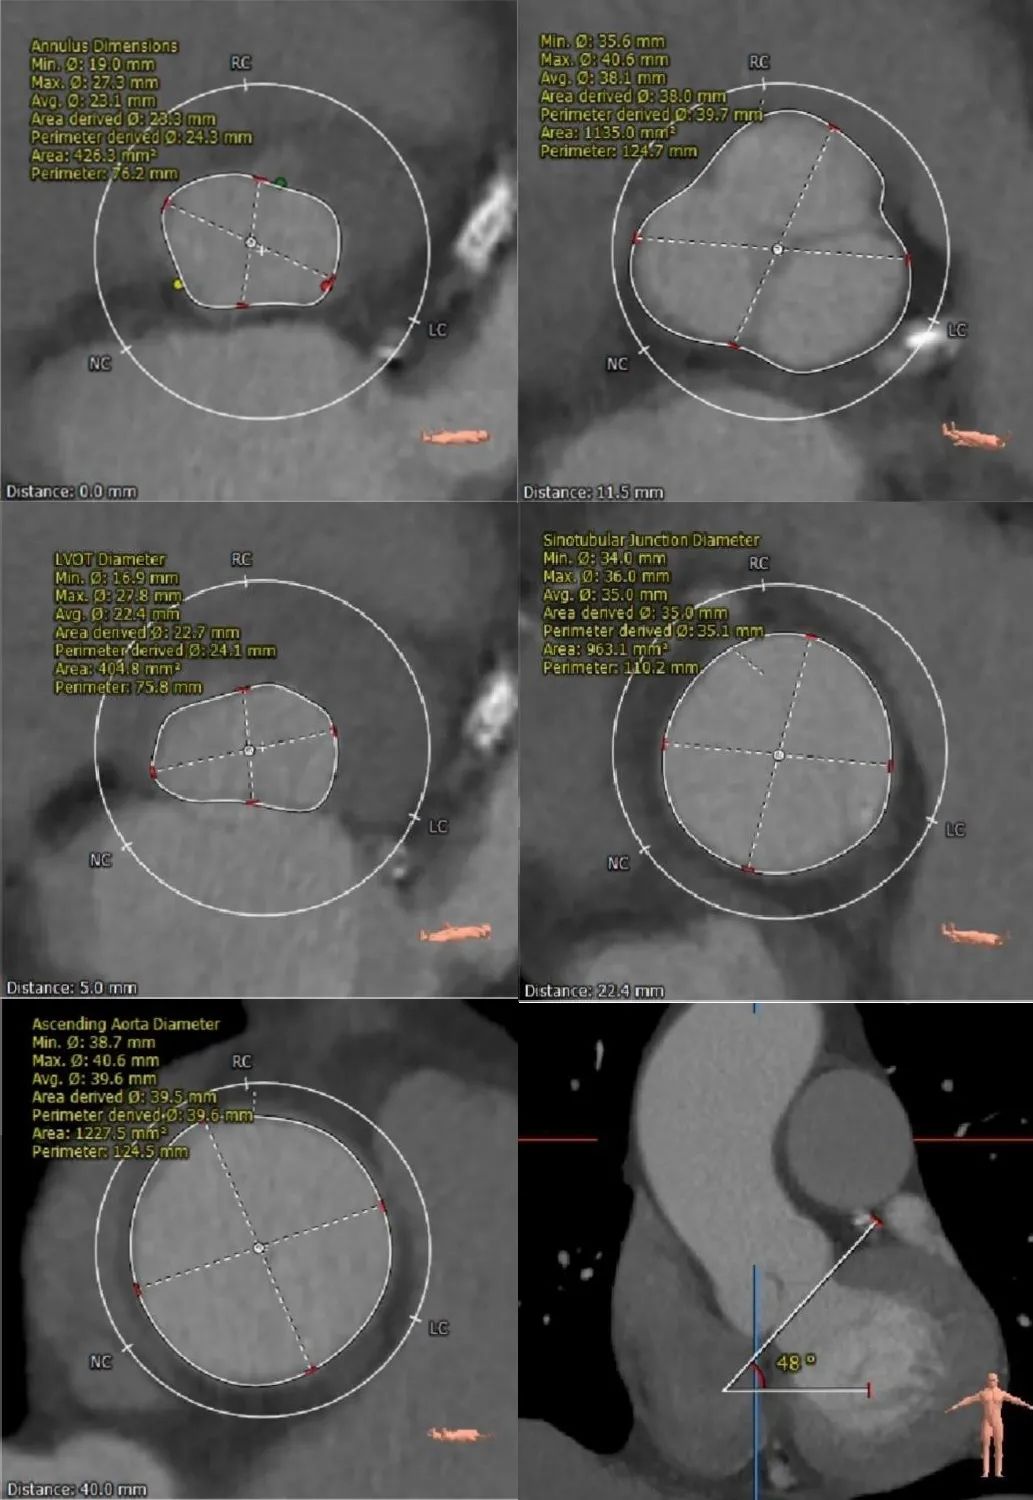

主动脉根部测量:

这是一例很有挑战性的病例,单纯AR,无狭窄无钙化,LVOT小于瓣环,心肌肥厚,容易从下向上挤压瓣膜。瓣膜在释放锚定时会有很大困难。只能依赖于自膨瓣的oversize和释放时精准定位。所以术前评估和瓣膜型号的选择尤为重要。这个病例的瓣环平均径是24.3mm,通常返流的病例在选择瓣膜型号时会比瓣环oversize15%左右,评估后,选择了29号瓣膜比较合适。不仅仅要评估瓣环,我们通过评估主动脉根部整体的结构,精准测量,为手术做了充足准备。术中,我们采用沛嘉公司的瓣膜产品,利用了LVOT,瓣环,STJ,升主动脉多平面立体锚定来协助瓣膜的固定,同时沛嘉瓣膜及输送系统的表现都非常优异。输送器柔软,轻松过弓,定位精准,释放过程容易掌控,整个过程流畅一气呵成。为我们国产瓣膜产品感到骄傲,也希望沛嘉公司能给我们带来更多更好的产品,为临床医生提供更多治疗方案,造福患者。